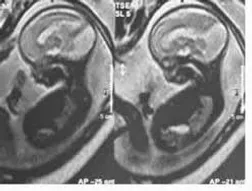

*Hamilelik döneminde prenatal ultrasound